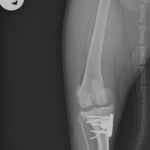

膝蓋骨内方脱臼+前十字靭帯断裂 PGR#21+CBLO #251

過去に膝蓋骨内方脱臼G4で手術を受けている患者さんが、急に跛行を呈するようになったとの事。関節炎が顕著であり、前十字靭帯断裂の併発も疑われます。ファットパッドサイン陽性、脛骨圧迫試験陽性、脛骨ピボット圧迫試験陰性でした。大腿骨滑車のリプレイスメントとCBLOで対応しました。